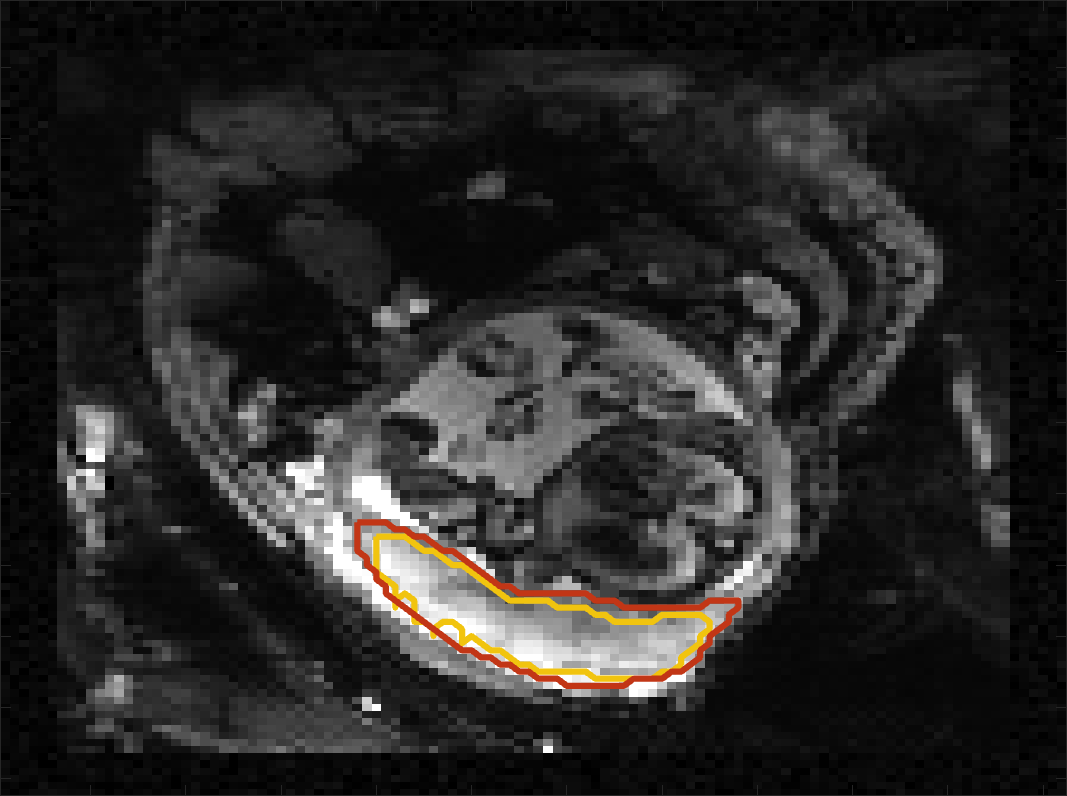

Figure 4 compares the predicted label maps with ground truth on subjects with increasing Dice scores using the BW-CE model. The model accurately identifies the location of the placenta, but in the worst cases misses boundary details.

BOLD Time Series Evaluation

Figure 5 presents example predicted segmentations at multiple points in the BOLD MRI time series for subjects. The predicted segmentations are robust to large fetal deformations and placental signal changes. Figure 6 (top) presents distributions of Dice score between predicted label maps of consecutive frames in the BOLD time series for all subjects in the test set. Distributions have high medians (Dice ) for all but one case, with high density at high Dice scores (Dice ). Dice differences are highly affected by fetal and maternal motion that cause placental deformation. We visually verified that modest drops in Dice () were mainly due to fetal motion, but subjects had a small number of frames with large drops (Dice ) that were caused by errors in the produced label maps. Figure 6 (bottom) shows D models of failed segmentations from two subjects from frames with Dice . Our model omitted parts of the placenta for Subject and added a large region for Subject . In practice, these failures ocurred in a small number of frames, of frames for Subject and of frames for Subject . Overall, predicted label maps are consistent between consecutive volumes of the MRI time series, achieving a Dice of and a BOLD difference of . The small differences between the relative mean-BOLD values suggest these produced segmentations may be suitable for research studies assessing placental function.